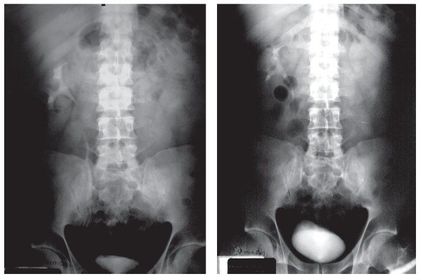

¿ Qué se puede encontrar en la urografía excretora, la tomagrafía o la resonancia magnética ? Deformidades y obstrucciones; las calcificaciones y estenosis ureterales son datos sugestivos de la enfermedad.

¿Qué porcentaje de Tb extrapulmonar representa la de articulaciones y huesos? El 10%

¿Cuáles son las articulaciones afectadas con mayor frecuencia? Las que soportan peso como lo son: la columna vertebral, cadera y rodillas.

¿Qué sitio es el más afectado en Tb vertebral en niños? La columna vertebral torácica

¿ Qué sección de la columna vertebral se ve más afectada en adultos? La porción inferior de la columna torácica y la porción superior de la lumbar.